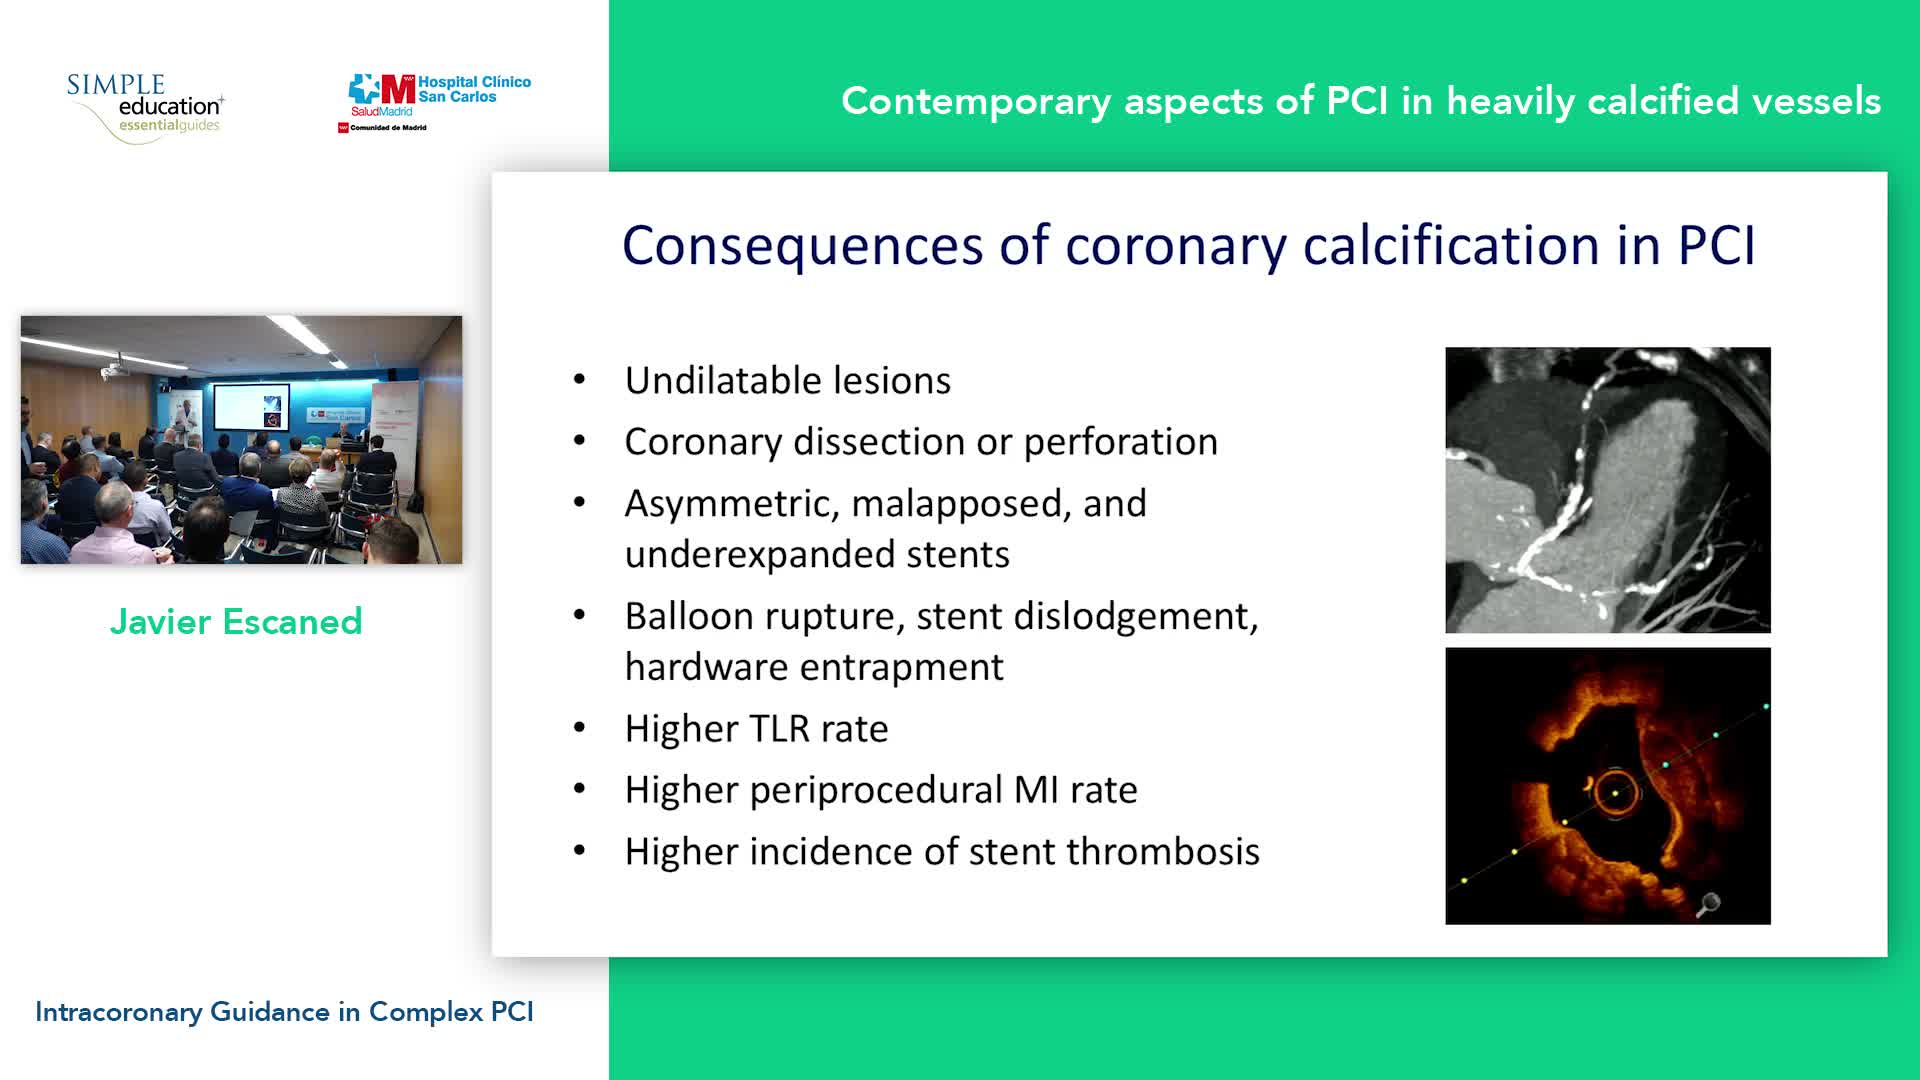

Advanced PCI Course Content

Best practices and personalised medicine in complex PCI - Prof Javier Escaned